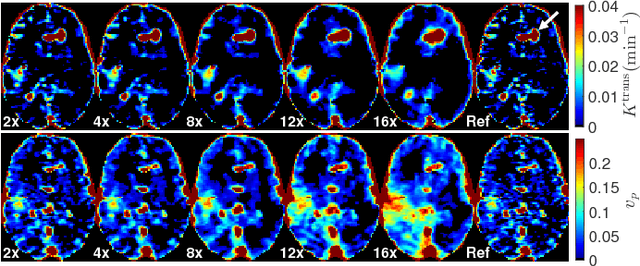

Abstract:Perfusion-weighted magnetic resonance imaging (MRI) is an imaging technique that allows one to measure tissue perfusion in an organ of interest through the injection of an intravascular paramagnetic contrast agent (CA). Due to a preference for high temporal and spatial resolution in many applications, this modality could significantly benefit from accelerated data acquisitions. In this paper, we specifically address the problem of reconstructing perfusion MR image series from a subset of k-space data. Our proposed approach is motivated by the observation that temporal variations (dynamics) in perfusion imaging often exhibit correlation across different spatial scales. Hence, we propose a model that jointly penalizes the voxel-wise deviations in temporal gradient images obtained based on a baseline, and the patch-wise dissimilarities between the spatio-temporal neighborhoods of entire image sequence. We validate our method on dynamic susceptibility contrast (DSC)-MRI and dynamic contrast-enhanced (DCE)-MRI brain perfusion datasets acquired from 10 tumor patients in total. We provide extensive analysis of reconstruction performance and perfusion parameter estimation in comparison to state-of-the-art reconstruction methods. Experimental results on clinical datasets demonstrate that our reconstruction model can potentially achieve up to 8-fold acceleration by enabling accurate estimation of perfusion parameters while preserving spatial image details and reconstructing the complete perfusion time-intensity curves (TICs).